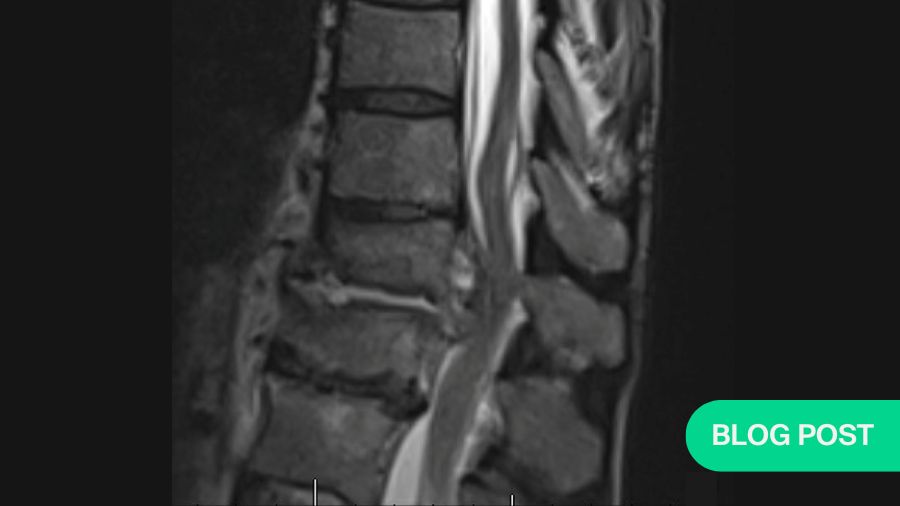

Upon presentation to the ED, he was initially treated with supportive measures/pain control for his back pain. His mention of fevers/chills prompted the ED staff to draw inflammatory labs, which were elevated. Additionally, blood cultures were draw, which eventually grew bacteroides. Due to the elevated blood cultures, and his unrelenting low back pain despite pain control efforts, advanced imaging was obtained. Noncontrasted computed tomography (CT) scan of his spine showed age-appropriate degenerative changes, but was negative for acute findings, and did not show any bony destruction (Figure 1a). A noncontrasted magnetic resonance imaging (MRI) scan of the spine was obtained, which demonstrated a small prevertebral collection without neural compression, and slight end-plate hyperintensity at the L3-L4 level. Additionally, there were L4-L5 and L5-S1 Modic changes (Figure 1b).